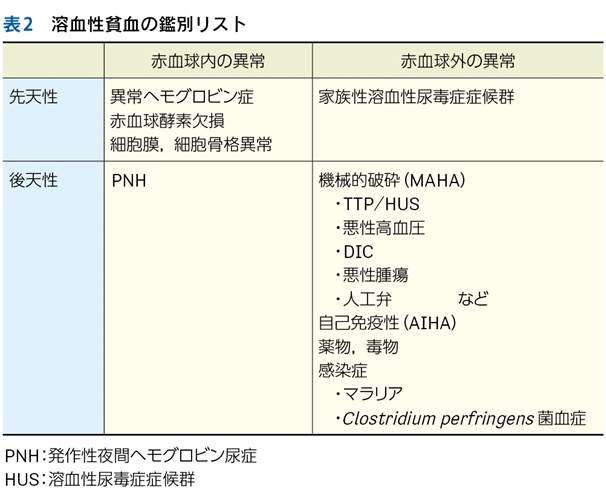

・ Hb低下,LDHと間接ビリルビンの上昇,ハプトグロビン低下:溶血性貧血

▶ 症候群名がつくことで,1つ1つのプロブレムを個別に扱うよりも認知負荷がぐっと減るとともに,狭く特異的な枠組みで考えることができる。また,症候群名がつけば検索によりその症候群をきたす疾患一覧を得ることは格段に容易になる。まさに「扱いやすく」,フレーミングに用いる「一等星」となる概念である。筆者は可能な限り,患者のプレゼンテーションを症候群として表現するように努めている。

▶ 注意したいのは,「症候群名」をもって「診断名」と混同しないことだ。急性心不全,急性上気道炎,溶血性貧血という言葉が疾患名のように扱われ,これらの名前がついたことをもって「診断」とされることがしばしばあるが,実際にはこれらは状態名であり,複数の原因疾患を含む「くくり」の名前であって,最終的な診断名ではない。さらに突き詰めて,「急性心不全を合併した急性心筋梗塞」「インフルエンザウイルス感染症」「全身性エリテマトーデス(systemic lupus erythematosus;SLE)に合併した自己免疫性溶血性貧血」などといった疾患名へと還元されていかなければならない。